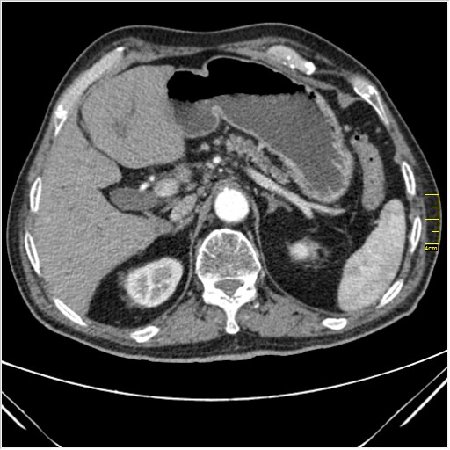

Мужчина 62 года с желтухой

Опухоль головки поджелудочной железы, расширение холедоха и панкреат. протока (Double Channel sign)

Карциномы панкреас гиподенсны на КТ с болюсом, т.к. содержать много соединительной и фиброзной ткани, в отличие от нормальной ткани железы, которая (как любая железа) хорошо васкуляризирована. Поэтому если видим в панкреас солидное гиподенсное образование - всегда настораживает на предмет рака. Второй момент: обязательная оценка взаимоотношения опухоли к ВБА и ВБВ, на предмет оценки операбельности.

pancr7.JPG

pancr7.JPG (62.38 КБ) 2898 просмотров